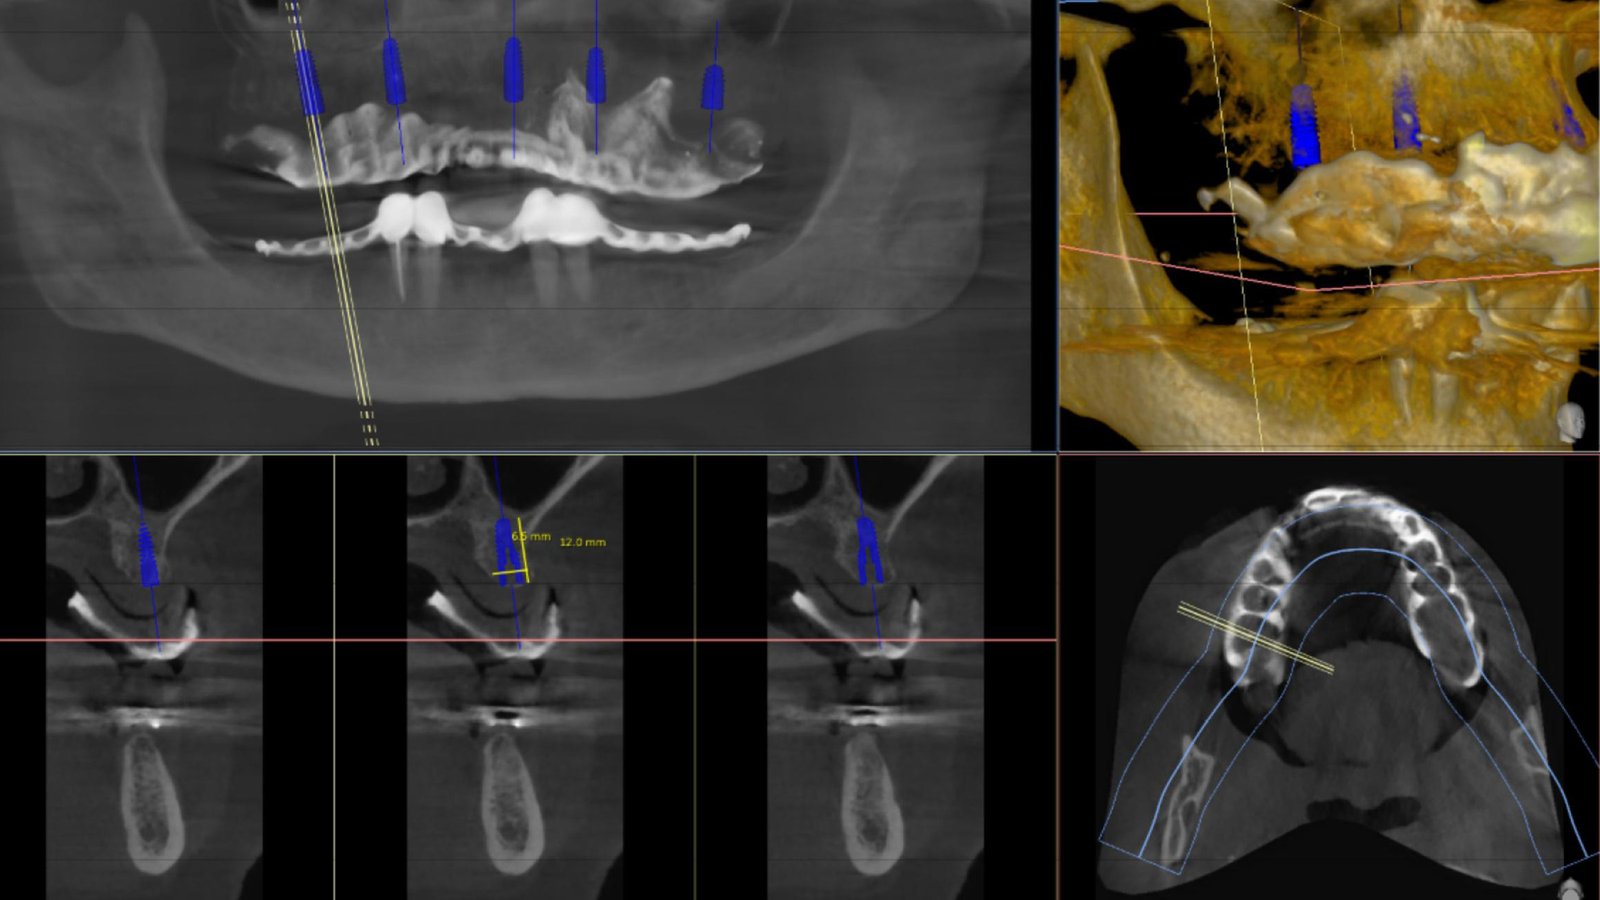

Ψηφιακή ανάλυση

Ψηφιακή ανάλυση και σχεδιασμός θεραπείας.

3D ανάλυση οστού.